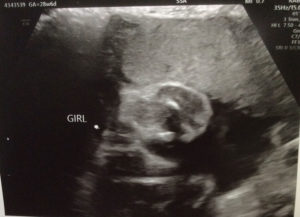

Mi nombre es Maria mi reversión de ligadura fue en 4/18/2017 tres meses después tuve mi primer embarazo que terminó en aborto a las 7 semanas Esperé dos meses y tuve otro embarazo que también terminó en aborto a las 12 semanas fueron dos embarazos sin bebé por que nunca se formó el embrion ahora embarazada otra vez de una niña tengo 33 semanas mi niña nacerá en diciembre 2018 estoy muy feliz gracias a dios al Dr. Monteith y a todo su personal por este milagro muchas gracias doctor Monteith.